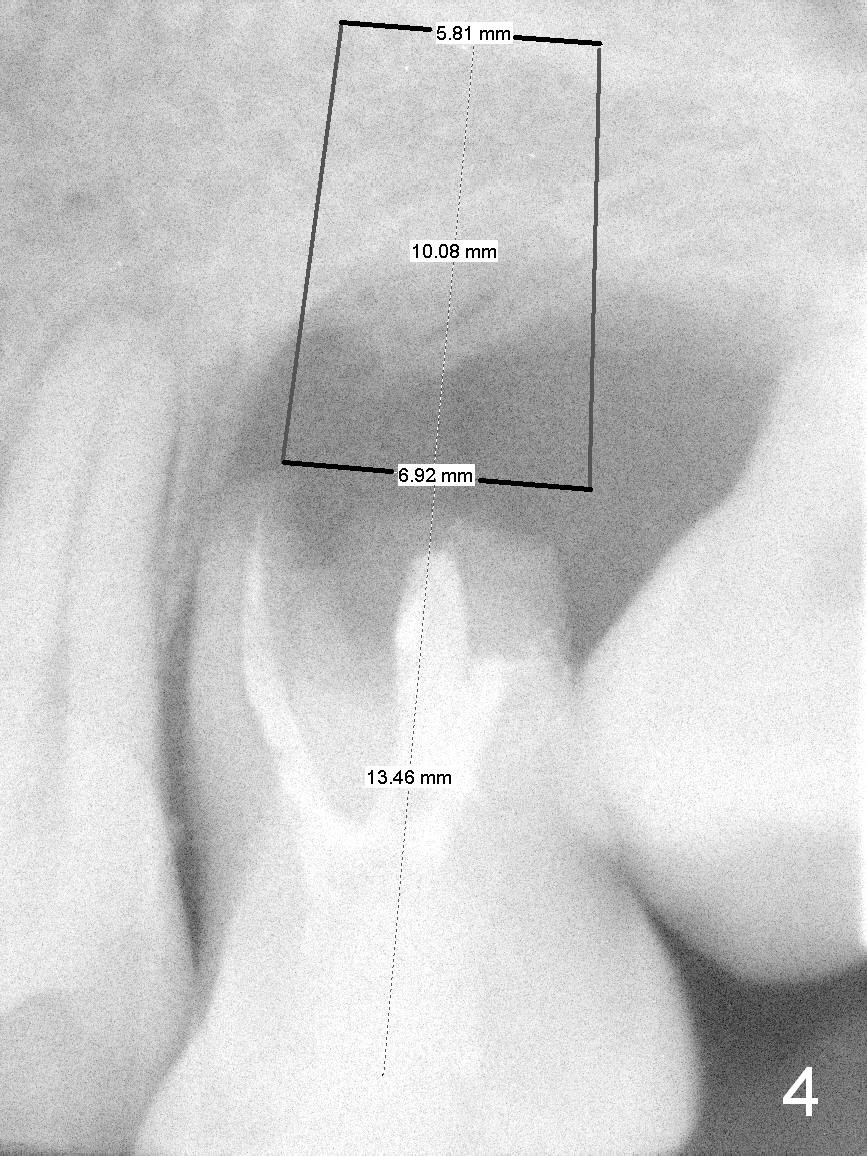

A 42-year-old man (XK) has perio-endo disease at the tooth #14. After root canal therapy (Fig.1), the tooth remains nonsalvageable. The bone loss is extensive (Fig.1 *) and uneven (more bone mesially than distally) after extraction (2% Xylocaine/1:50,000 Epinephrine). A bone-level implant is placed in an ideal depth (Fig.3 UF; Fig.4 SM), irrelevant of the gingival margin, first. Place bone graft distally (Fig.3 red circles) before choosing a proper abutment. For example, there is plenty of combination to choose cuff and abutment lengths for a SM or UF implant (Fig.4).